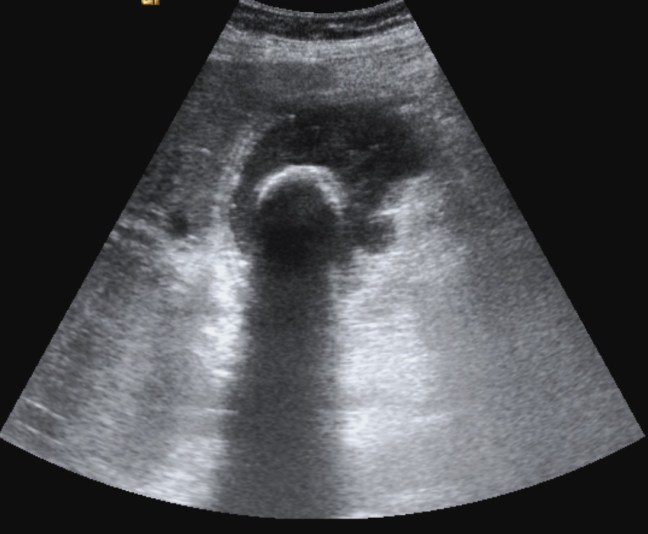

Se realiza ecografía abdominal:

En sucesivos cortes observamos lo siguiente:

Se observa una mala evolución radiológica. Dada la clínica del paciente y los hallazgos ecográficos podemos concluir que estos hallazgos son compatibles una colecistitis xantunogranulomatosa litiásica sobreinfectada (que se confirmó posteriormente con anatomía patológica).